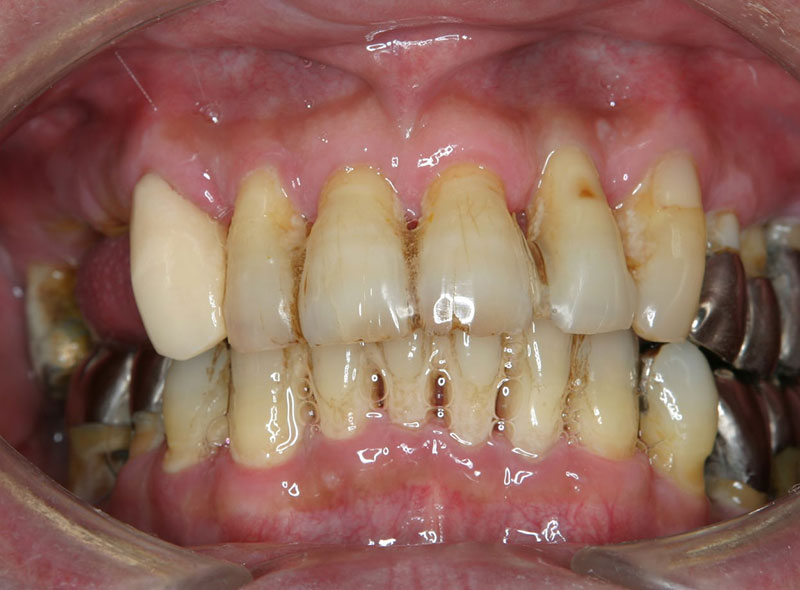

歯周病は痛みなどの自覚症状があまりない病気で、サイレント・ディジーズと呼ばれています。自覚症状が出る頃にはかなり悪化しているケースが多く、歯を支えている骨が半分以上溶けている事もあります。

歯周病で一度失った骨は基本的には元に戻りません。歯周病の治療は歯周病の原因を除去してこれ以上骨が溶けないよう口腔環境を良くする治療で、重度の歯周病をほっておくとどんどん骨を失っていきます。歯槽骨(歯を支える骨)再生療法という治療方法もありますが、10失われた骨が10戻ることは無く、3〜5ぐらい骨を再生する可能性があるという治療方法なので、基本溶けた骨は元に戻らないと思っていたほうがいいです。

悪くなってから治療を繰り返していると、歯周病で失った骨は戻ってこないので、悪くなるたび歯を支える骨は失われていき、結果早く歯が抜けてしまいます。